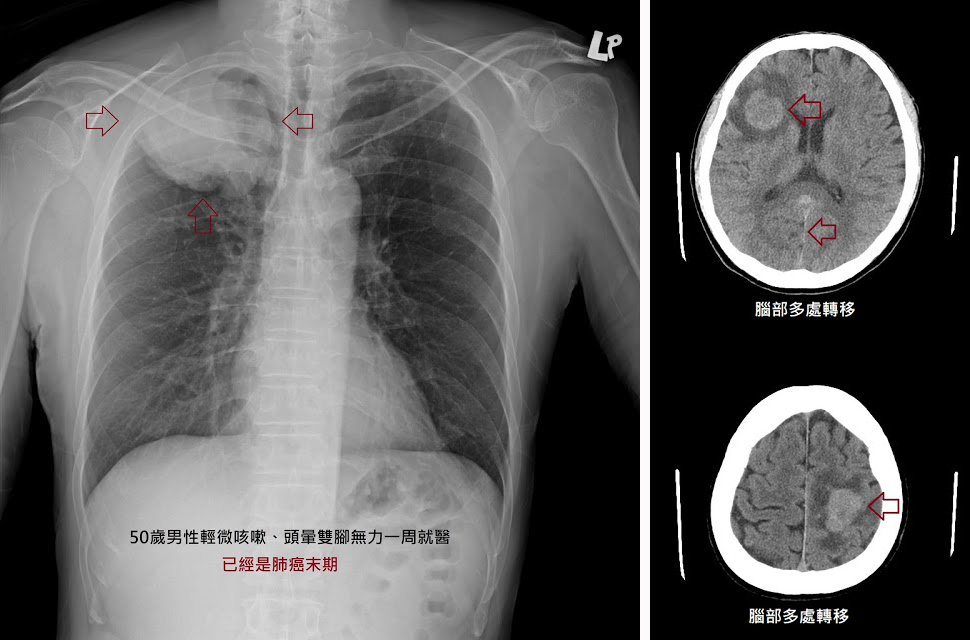

雪上加霜的是,多数患者出现症状就医时,肺癌已处于晚期阶段,治疗选择受限,疗效大打折扣。

但若能在早期揪出肺癌,一切将截然不同,治疗手段会更加丰富且更易奏效。